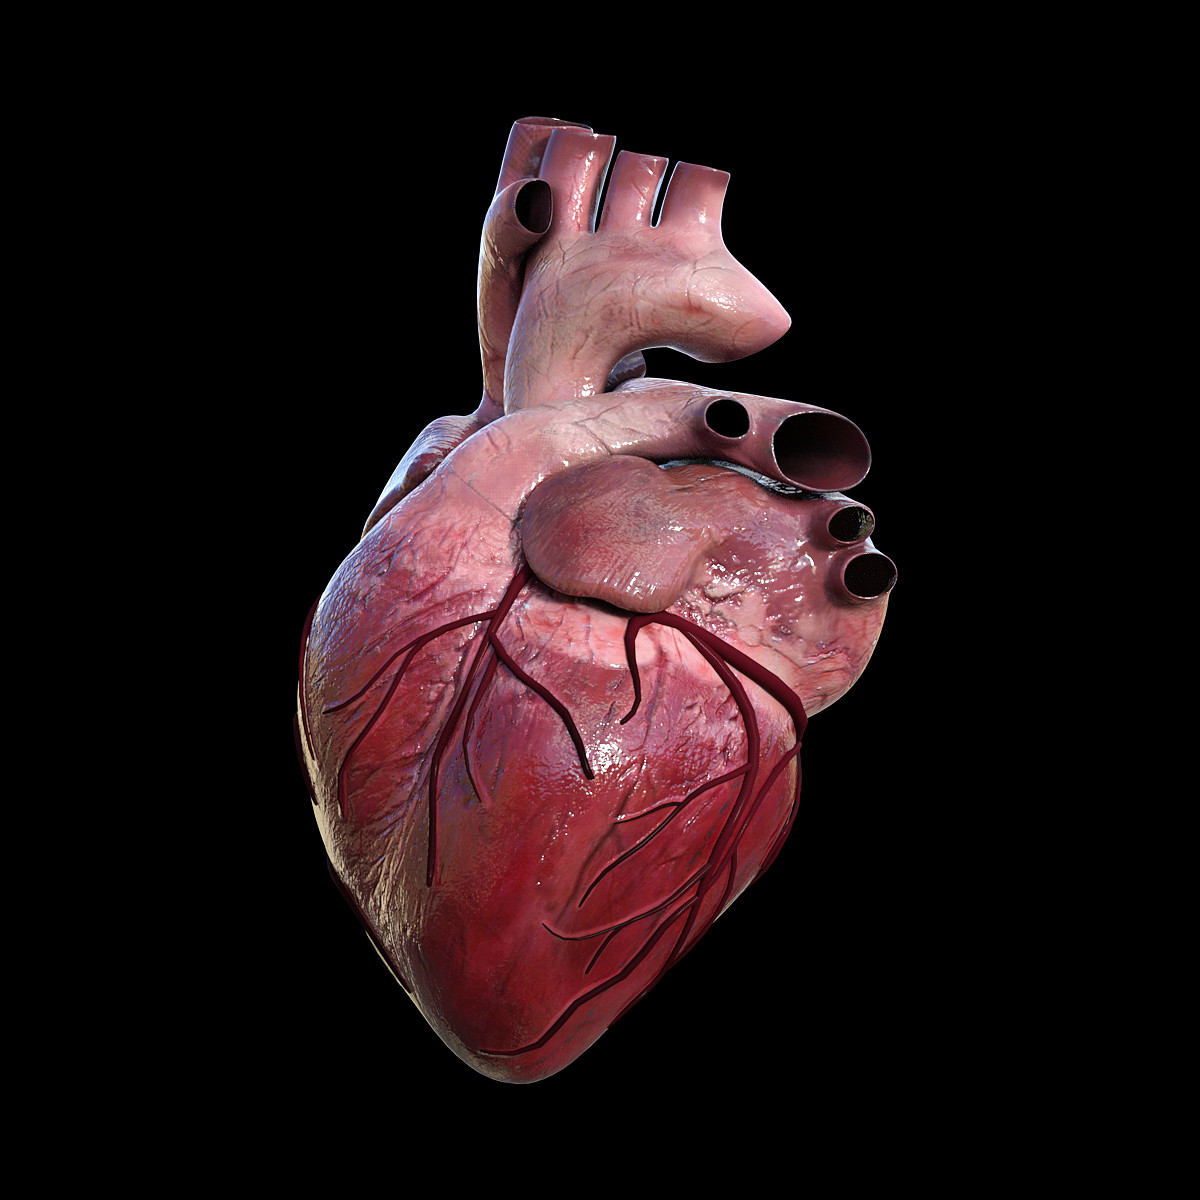

Human Heart 3D stock vector. Image of doodle, organ, conceptual - 43760249

Human Heart Sketchbook study by bluesytealyren on DeviantArt | Human heart drawing, Anatomical  3d human heart

3d human heart  Animated Realistic Human Heart - Medically 3D asset

Heart by Rustamova on @DeviantArt | Anatomical heart art, Anatomy art, Heart drawing  3d human heart

3d human heart  Human Heart Pencil Drawing at GetDrawings | Free download

Human Heart Pencil Drawing at GetDrawings | Free download  3d human heart

3d human heart  3d human heart

3d human heart  3d human heart anatomy model

3d human heart  Realistic detailed 3d human anatomy heart Vector Image

3d human heart  Human Heart Study Drawing, HD Png Download - kindpng

3d human heart  Royalty Free Human Heart Clip Art, Vector Images & Illustrations - iStock